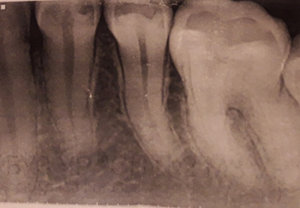

Здравствуйте! Подскажите пожалуйста, очень болит зуб вторую неделю! Нахожусь временно не в своём городе, тут гинеколог и стоматолог в одном лице. Скоро домой, договорился со своим лечащим врачом, примет по приезду 28/02, но боюсь не доживу, каждый день всё больнее и больнее. Предложили вырвать его, но он не шатается, стот крепко без кариеса вылеченный. Жевательный зуб 7, под десной сначала был красным, теперь весь зуб странного, бледного цвета. Ноет сильно пью обезболивающее. Есть снимок. Помогите пожалуйста.